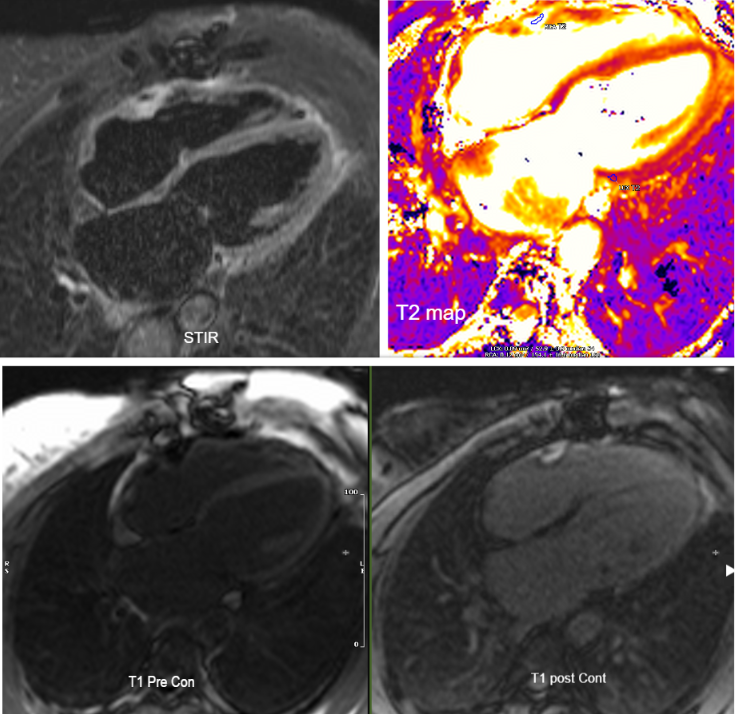

This picture is a collective of the CMR findings of the RCA perivascular inflammation, as shown to have high signal in the STIR and T2 map, suppression on T1 sequence enhancement in the T2 post contrast